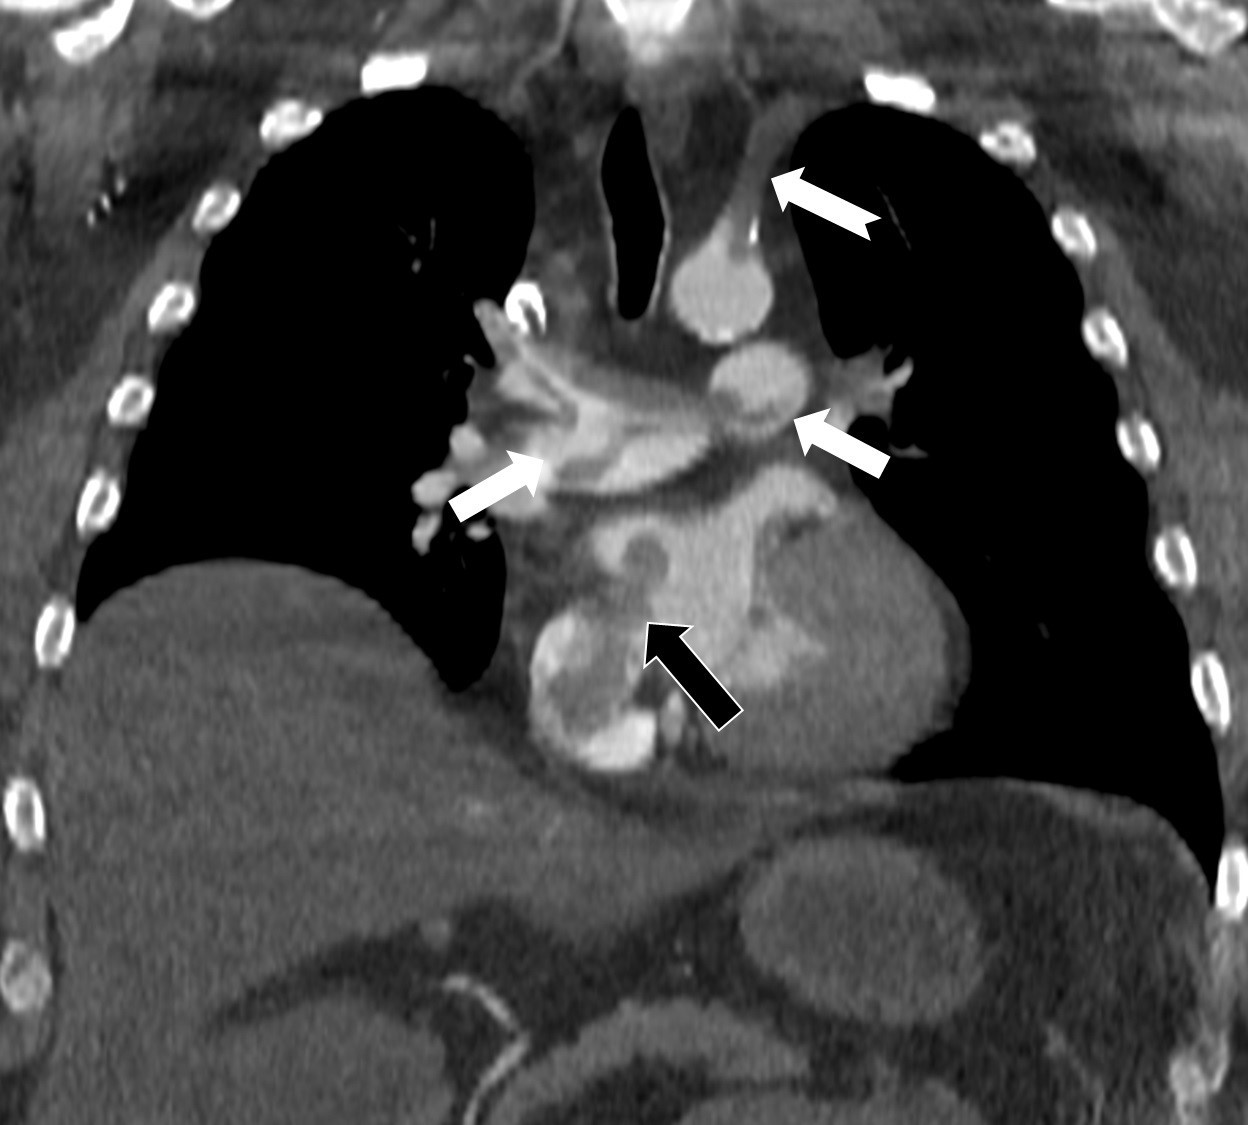

Bir dönem Özel Denizli Tekden Hastanesi’nde de görev yapan Prof. Dr. Nevzat Karabulut’un yaptığı çalışmada; akciğerin bilgisayarlı tomografi anjiyografisi sayesinde toplar damarlardan kaynaklanan pıhtının akciğer damarlarını tıkaması yanında, kalpteki delik nedeniyle kalbin sağ tarafından sol tarafına geçerek ana atardamara ulaştığı ve sol kol damarını tıkadığı gösterildi.

Emboli görüntülemesi konusunda çok sayıda bilimsel çalışması bulunan Prof. Dr. Karabulut, genelde bacak damarlarından kaynaklanan pıhtıların ölümcül olabilen akciğer embolisine yol açması yanında, kalp deliği olan hastalarda ana atardamar yoluyla beyin, kol ve bacak gibi vücudun diğer bölgelerine de geçerek ani damar tıkanmasına (paradoks emboli) bağlı bulgulara yol açtığını belirtti. Prof. Dr. Karabulut’un çalışmasında nedeni bilinmeyen pıhtı atmalarında kalpteki gizli deliklerin mutlaka araştırılması gerektiği vurgulanarak ekokardiyografi ve bilgisayarlı tomografi tetkiklerinin erken ve doğru tanı koymada hayat kurtarıcı rolüne dikkat çekildi.